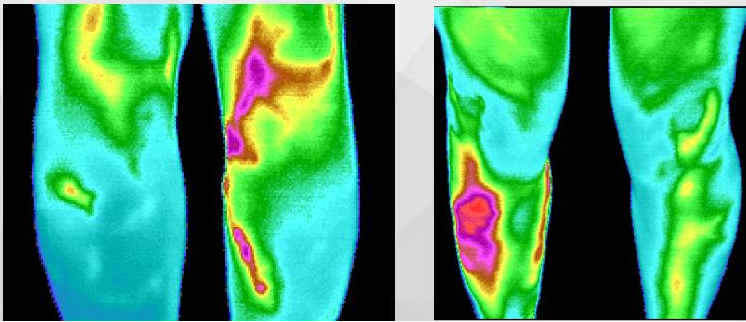

让我们一起来看看正常机体状态下的热图和异常机体状态下的热图吧:

下肢静脉曲张